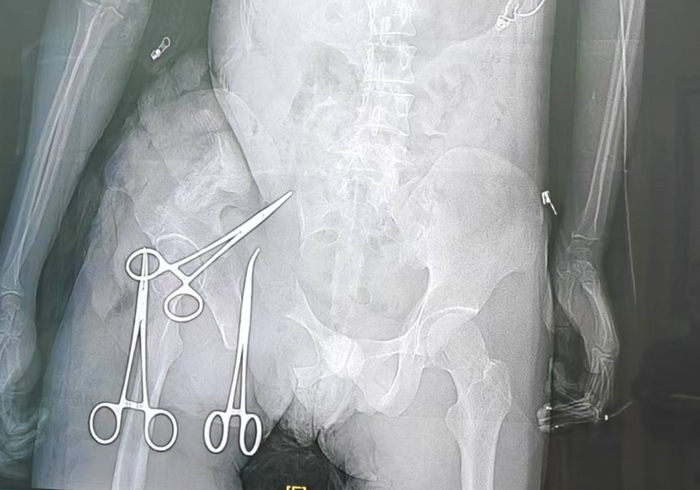

市一医标准化的创伤复苏单元和创伤重症病房,是全市各级医院创伤中心建设的样板 。 会议公布的数据显示,自惠州市一医牵头全市创伤体系建设以来 ,目前已初步构建起以市一级创伤中心为龙头 、县二级创伤中心为骨干 、基层医疗机构为网底的“三级创伤救治网络”。同时得益于惠州市交通创伤救治形式及警医联动促进交通伤救治的特点 ,逐步强化县区级及基层创伤中心救治能力 ,形成县区全域联动覆盖的良好局面。

市创伤专业质控中心指导创伤单元建设,图为龙门县人民医院创伤单元 “我们过去常谈‘黄金一小时’ ,但真正决定患者生死的除了黄金一小时,还需要强大的外科手术团队、重症团队保障创伤救治。”惠州市一医副院长、急诊医学科学科带头人 、市创伤专业质控中心主任委员李王安指出,“体系建设的目标,就是通过标准化流程和同质化培训平台,将优质医疗资源前置,本尊科技压缩一些不必要的环节,确保患者在市内任何一个网络节点都能得到最及时 、最规范的处置。”